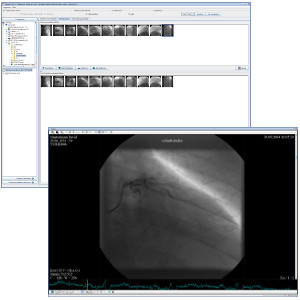

TM-PACS

Lets you compress, secure, store, and view x-ray images using cutting-edge display and viewing tools (zoom, magnifier, annotations, distance measurement, measurement tracking, etc.). The user can view coronarographic, PET, and nuclear medicine images at the same time, as well as more classic imaging (MRI, CT scan, ultrasound, etc.). The use of labels associated with the exams lets you create groups of exams and access them via one click. A personalised search system allows you to access the desired patient file or exam very quickly. The display is optimised to allow multi-screen display, as well as the integration of the RIS and PACS software installed on the same diagnostic stations.